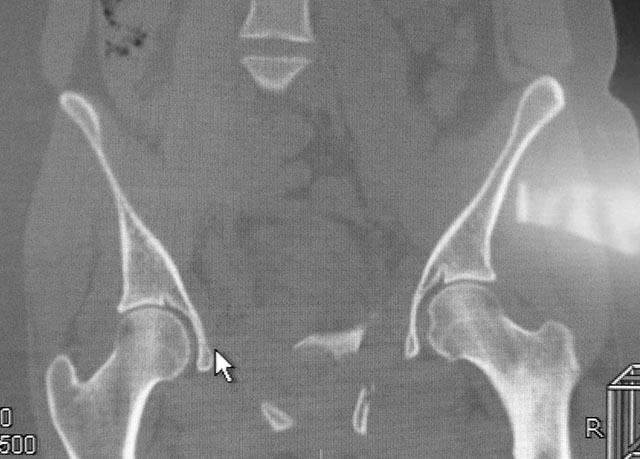

Женщина,21, социальна, без вредных превычек, сбита авто.

Кожа не повреждена. Других повреждений нет. Гемодинамически стабильна. травме 2 сут. Планируем спереди открыто через Stoppa, далее сзади крестец и ость закрыто (крестец может через обе массы?). Интересует мнение по альтернативным вариантам и по предложенному (tricks and shots). Заранее благодарен.

PS Только часть скринов с body scan, один с контрастированием пузыря.